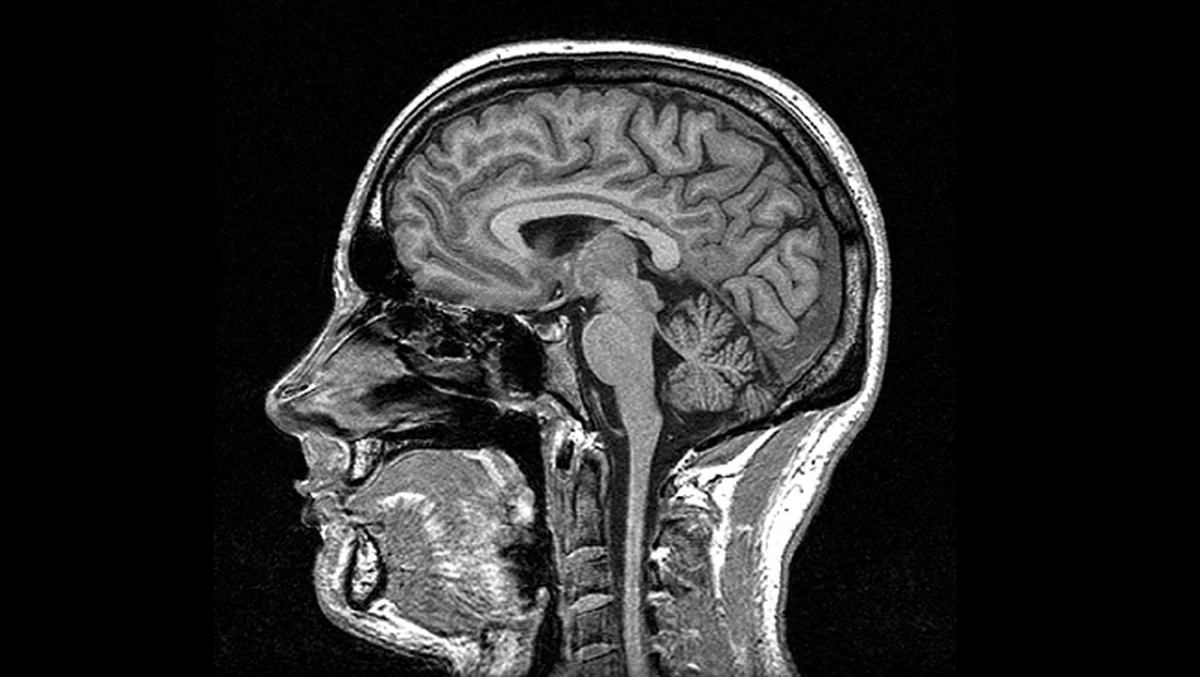

Okazuje się, że nawet umiarkowane spożycie alkoholu może być dla naszego mózgu mniej obojętne, niż sądziliśmy. To odkrycie dotyczy nie tylko osób nadużywających trunków, ale większości z nas, którzy sięgają po piwo czy drinka sporadycznie.

Naukowcy przyjrżeli się mózgom osób, które mieszczą się w powszechnie uznawanych normach – do 60 drinków miesięcznie dla mężczyzn i 30 dla kobiet. Wyniki badań opublikowane w czasopiśmie Alcohol mogą być dla wielu zaskoczeniem.

Badacze zauważyli bezpośredni związek między spożywaniem alkoholu a dwoma kluczowymi parametrami:

- Zmniejszony przepływ krwi: Mózg jest niedotleniony, co utrudnia usuwanie produktów przemiany materii.

- Cieńsza kora mózgowa: To właśnie ta warstwa odpowiada za nasze najwyższe funkcje myślowe i podejmowanie decyzji.

Co ciekawe, zmiany te są bardziej wyraźne u osób starszych. Wygląda na to, że nawet jeśli nasz organizm wydaje się „neutralizować” negatywne skutki w młodości, uszkodzenia kumulują się z biegiem lat.